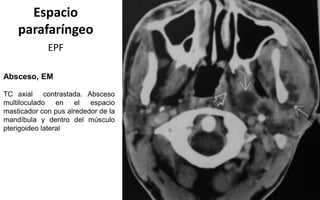

Absceso, EM

TC axial contrastada. Absceso

multiloculado en el espacio

masticador con pus alrededor de la

mandíbula y dentro del músculo

pterigoideo lateral